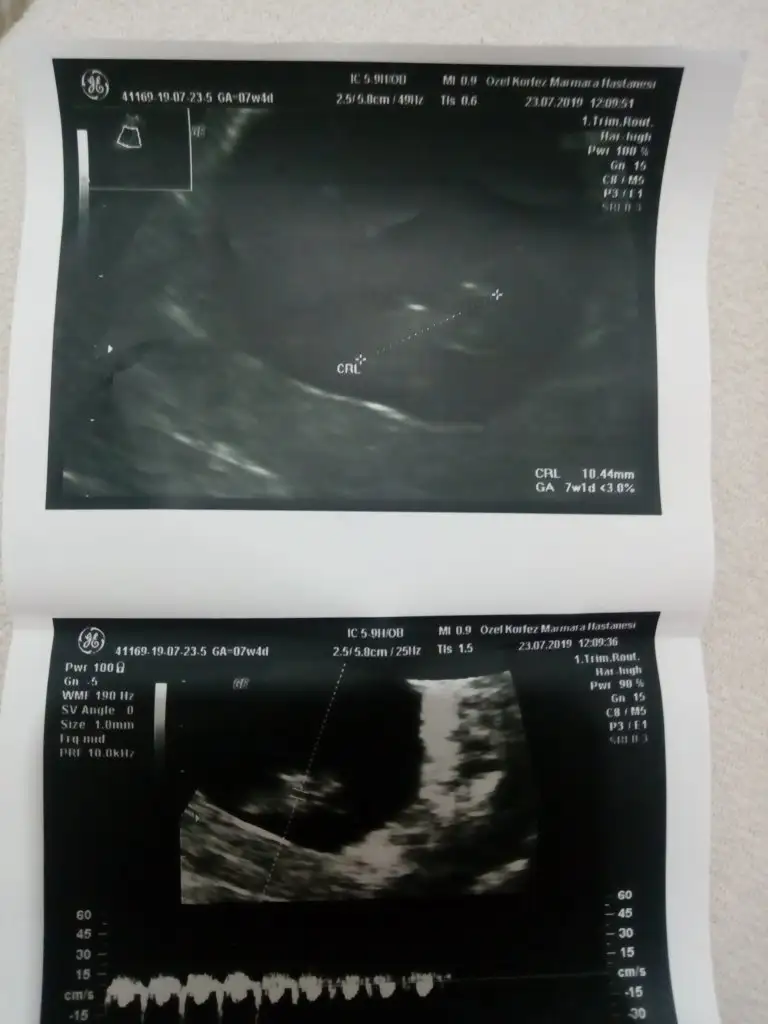

6. 7 haftalık görüntü var mıBende tahmin alabilirmiyim 9 haftalk katindan

6. 7 haftalık görüntü var mı

Buna göre kızEki Görüntüle 2301166 7 haftalik vajinal ultrason